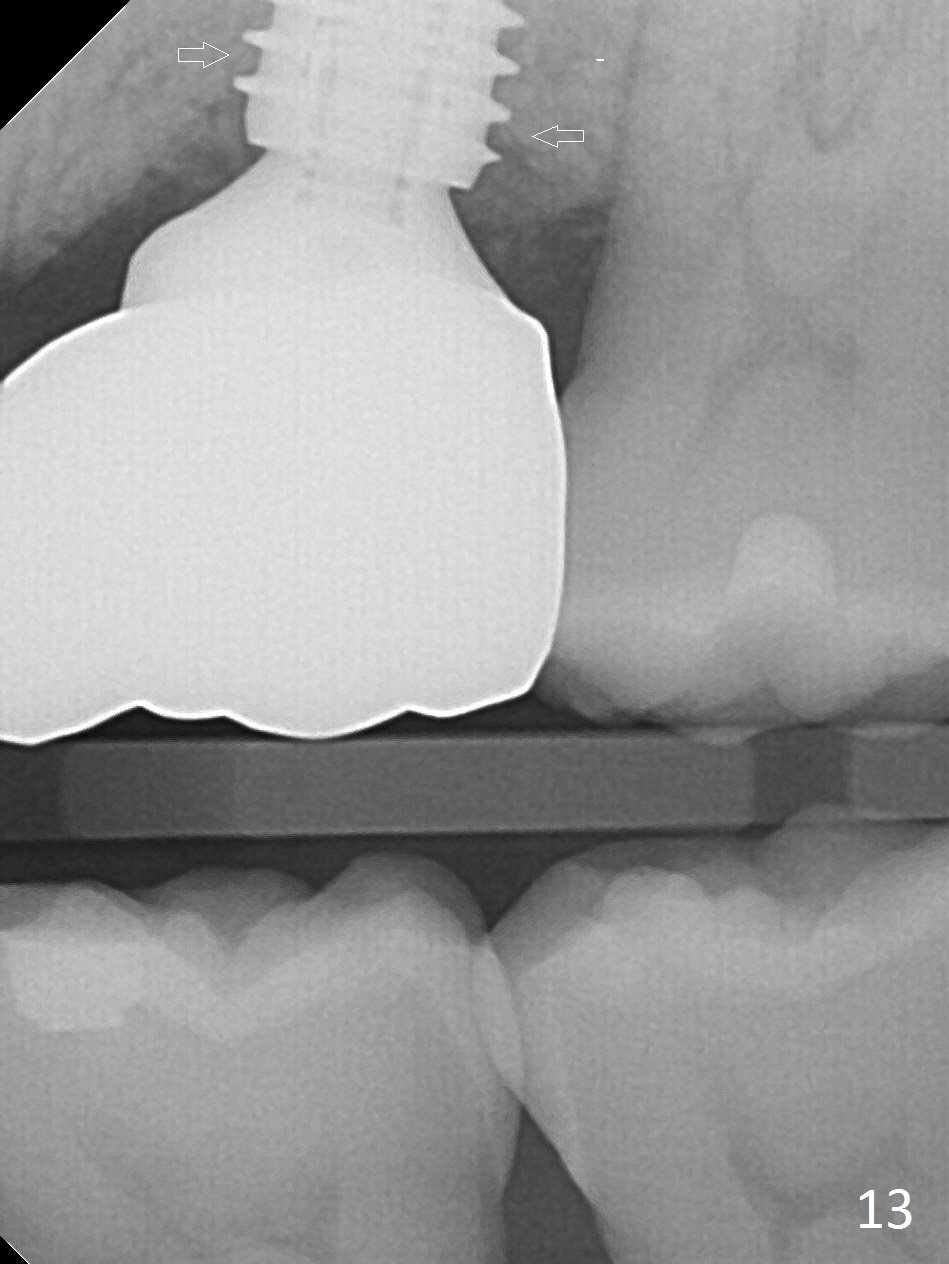

The patient experiences palatal gingival tenderness 5 months post cementation, probably due to loose proximal contacts and excessive use of floss. PA shows new normal bone next to the upper threads (Fig.12 arrow), while new less dense attached to the most coronal threads (*). BWs (Fig.13,14) shows that new bone has grown into the area between the most coronal 2 threads (arrows). When the crown and abutment are removed, the gingiva looks normal except minor laceration buccally. A 7.5x4 mm healing abutment is placed. If the infection resolves, pick up impression will be taken to add porcelain to the proximal surfaces to prevent food impaction.